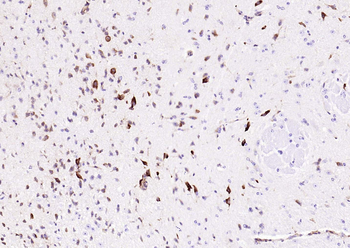

100 μl, 50 μl, 200 μl - ATF4 Recombinant Rabbit Monoclonal Antibody [orb704304]Featured

FC, ICC, IF, IHC-Fr, IHC-P, WB

Human

Mouse

Rabbit

Recombinant

Unconjugated

50 μl, 100 μl - MARK3 Recombinant Rabbit Monoclonal Antibody [orb704310]Featured